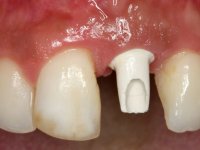

A paciente apresenta um desvio da linha média superior de 6 mm para a esquerda. Resultado da ausência do incisivo central superior esquerdo, os dentes adjacentes inclinaram mesialmente para esta zona, limitando o espaço disponível para a reabilitação prostodontica. Existe uma significativa desarmonia dentária negativa no arco maxilar como resultado da ausência do 21, ausência do primeiro pre-molar com um espaço residual, significativa redução coronária do segundo pre-molar direito, migração dos dentes posteriores para os espaços não preenchidos e uma mesialização molar superior esquerda e direita com uma relação molar em Classe II. Ambos os caninos esquerdo e direito mostram uma relação Classe II na posição de inter-cuspidação máxima. A paciente apresenta uma linha de sorriso média, um biótipo gengival médio grosso, apresenta uma correcta higiene oral sem doença periodontal. Não apresenta hábitos para –funcionais. O exame radiográfico mostra uma significativa inclinação dos eixos dos dentes 11 e 22 com espaço entre a porção apical das raízes. A análise cefalométrica foi feita com o intuito de explorar a hipótese de conseguir arranjar espaço para a colocação de um implante e de uma coroa no local do dente 21. Finalmente a morfologia do osso residual presente na região anterior da maxila foi avaliado com uma TAC, revelando uma perda das dimensões da parede óssea vestibular.

2) Tratamento ortodôntico com o objectivo de criar espaço entre as raízes e as coroas dos dentes 11 e 22,

3) Colocação de um implante no espaço criado na zona do 21 associada a uma regeneração óssea guiada da zona,

4) Reabilitar prostodonticamente o implante com um coto de oxido de zirconio e uma coroa de cerâmica vítrea prensada de dissilicato de lítio no sentido de obter o resultado estético pretendido.